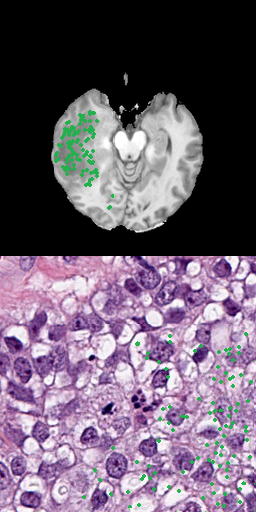

One approach is to use several positive points as input data that represent the goal label [8]. Using points as input is a precise method, allowing to preserve fine segmentation details but requires more annotation effort. When large areas are annotated, this is especially problematic. Figure 3 shows samples for using 3, 10, 50 or 100 points for the radiology and pathology data.

Refer to caption

(a) 3 positive points

(b) 10 positive points

(c) 50 positive points

(d) 100 positive points

Figure 3: Results for different number of positive points without bounding box